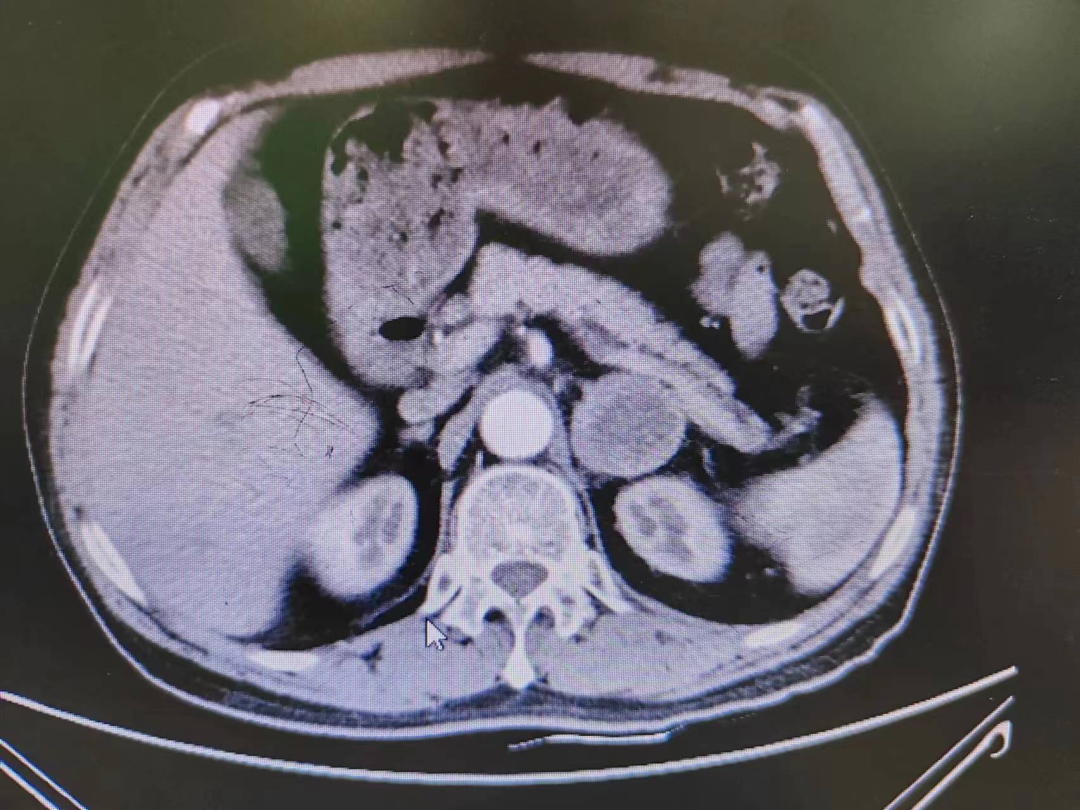

患者熊XX,67歲,因發(fā)現(xiàn)頭暈、頭痛曾多次于外院就診,到新橋醫(yī)院就診完善腎上腺CT考慮嗜鉻細(xì)胞瘤,既往有高血壓病史3年,血壓更高達(dá)230/120mmHg。我院高新區(qū)院區(qū)開診后,患者慕名而來。術(shù)前積極完善血尿兒茶酚胺代謝產(chǎn)物(MNS)均明顯升高,患者于我院高新區(qū)院區(qū)及江南院區(qū)泌尿外科積極控制血壓、心率、血糖,術(shù)前充分?jǐn)U容。

因腫瘤位置位于腎蒂周圍,術(shù)中觸碰腫瘤導(dǎo)致血壓明顯升高,血壓波動較大,腫瘤表面血供豐富,不僅需要手術(shù)醫(yī)生豐富的臨床經(jīng)驗(yàn)和高超的技術(shù)水平,也是對醫(yī)生心理素質(zhì)、勇氣和毅力的嚴(yán)峻考驗(yàn)。